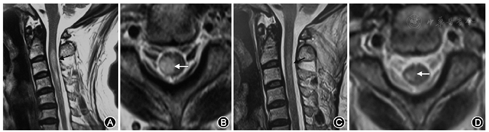

患者女性,59岁,主因"右颈部疱疹伴疼痛21 d,右肢麻木无力7 d"于2017年6月9日入院。患者于入院前21 d右颈部出现带状簇集性水疱伴烧灼、刀割样疼痛,当地医院诊断为"带状疱疹",予阿昔洛韦、甲钴胺、维生素B1口服,治疗后症状好转,局部疱疹结痂。入院前7 d无明显诱因晨起出现右肢麻木无力,上肢可抬起、能持轻物,下肢能站立及行走,伴头晕,无言语不清及饮水呛咳,无视物旋转,无头痛,无恶心呕吐,无视物成双,无耳鸣及听力下降,无大小失禁,无意识不清及肢体抽搐,未予诊治。患者于入院前1 d上述症状加重,右上肢不能持物,右下肢不能站立及行走,遂就诊于我院,查头颅MRI示未见新鲜梗死灶,给予疏血通治疗。治疗后患者症状无好转,为进一步诊治收入我科。患者自发病以来精神、饮食、睡眠可,无发热,进食水无呛咳,大小便如常。既往有冠状动脉粥样硬化性心脏病史6年,脑梗死病史1年。否认高血压、糖尿病、心房颤动、胃炎、青光眼等病史;否认肝炎、结核等传染病史;否认手术史;否认外伤及输血史。否认毒物接触史;近期无疫苗接种史;否认食物过敏史。吸烟40年,20支/d,无饮酒嗜好。入院时体检:体温36.5 ℃,脉搏93次/min,呼吸18次/min,血压120/78 mmHg(1 mmHg=0.133 kPa)。右侧颈后部可见散在红色皮疹及少许结痂。神经科体检:意识清楚,言语流畅,双侧瞳孔等大等圆,光反应(+),眼球运动可,眼位居中,无自发性眼震及复视,视力、视野粗测正常,眼底双侧视乳头边界清楚,动静脉比例2∶3,双侧鼻唇沟对称,伸舌居中,颈软,右上肢肌力Ⅲ级,右下肢肌力Ⅲ-级,左肢肌力Ⅴ级,肌张力正常,腱反射(++),双侧巴宾斯基征(+),右侧C4~T3针刺痛觉过敏,左侧肢体痛觉减退。化验血常规、凝血功能、肝功能、肾功能、电解质、心肌酶、血流变、尿常规、便常规未见明显异常。血脂:总胆固醇5.22 mmol/L(正常值0~5.18 mmol/L),LDL胆固醇3.45 mmol/L(正常值0~3.37 mmol/L),余未见明显异常。EB病毒DNA、巨细胞病毒DNA、单纯疱疹病毒DNA(血、脑脊液)检测均为阴性。血清免疫功能未见明显异常。血清及脑脊液水痘-带状疱疹病毒定性PCR法阴性。血清水痘-带状疱疹病毒抗体IgM阴性,血清水痘-带状疱疹病毒抗体IgG阳性。脑脊液涂片检查未见明显异常。脑脊液常规无色透明,潘氏试验阴性,总细胞数90×106/L,白细胞8×106/L。脑脊液生化未见明显异常。脑脊液细胞学涂片见个别淋巴细胞。细胞免疫荧光法(CBA法)检测血清AQP4抗体(亦称NMO-IgG)(+++)。颈椎MRI示C2~5水平髓内异常信号,建议增强检查(图1);C4/5、C5/6、C6/7椎间盘膨出。颈椎MRI增强示C2~5水平髓内异常信号,考虑炎性改变可能性大。自主神经功能检查示上下肢皮肤交感反射异常;R-R间期变化率未见异常。视觉诱发电位检查示双侧视路未见明显异常。胸片示主动脉硬化。颈部血管超声示颈动脉硬化,附壁斑块,右侧椎动脉开口处流速偏快。入院后予更昔洛韦抗病毒、神经妥乐平抗周围神经痛等对症治疗,予人免疫球蛋白35.0 g静脉滴注,连续5 d。予甲泼尼龙500 mg静脉点滴,1次/d,持续3 d,然后顺序递减。经治疗10 d,患者病情好转出院。患者出院后9个月随访,右上肢肌力Ⅴ-级,右下肢肌力Ⅴ-级,MRI示C2~4水平髓内异常信号,较前明显缩小。

本例患者具有带状疱疹病毒感染病史,发病皮区相对应的脊髓节段受累,脑脊液带状疱疹病毒DNA检测阴性,血清水痘-带状疱疹病毒抗体IgM阴性,血清水痘-带状疱疹病毒抗体IgG阳性。患者脊髓炎出现在疱疹发病后3周,说明患者感染过水痘-带状疱疹病毒,该患者不符合带状疱疹脊髓炎的诊断标准,脊髓炎考虑不是带状疱疹病毒直接感染所致,可能与免疫介导有关,可考虑为带状疱疹病毒感染后脊髓炎。本例患者具备NMOSD的诊断标准,有1项核心临床特征性表现(脊髓炎),检测AQP4-IgG阳性,排除了其他诊断如肿瘤、风湿结缔组织病。故本例患者诊断为NMOSD。有关脑脊液AQP4-IgG的阳性检出率及其与血清AQP4-IgG之间的关系,目前尚无统一定论。2006年NMOSD的诊断标准认为,当脑脊液白细胞数>50×106/L,才有进一步检测脑脊液AQP4-IgG的意义[8]。血清AQP4-IgG阳性的NMOSD患者,脑脊液AQP4-lgG阳性检出率为45.1%[9]。本例患者即为血清AQP4-IgG阳性,而脑脊液AQP4-IgG阴性。